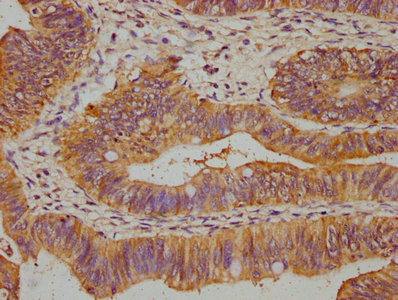

IHC image of PACO61722 diluted at 1:500 and staining in paraffin-embedded human colon cancer performed on a Leica BondTM system. After dewaxing and hydration, antigen retrieval was mediated by high pressure in a citrate buffer (pH 6.0). Section was blocked with 10% normal goat serum 30min at RT. Then primary antibody (1% BSA) was incubated at 4°C overnight. The primary is detected by a biotinylated secondary antibody and visualized using an HRP conjugated SP system.